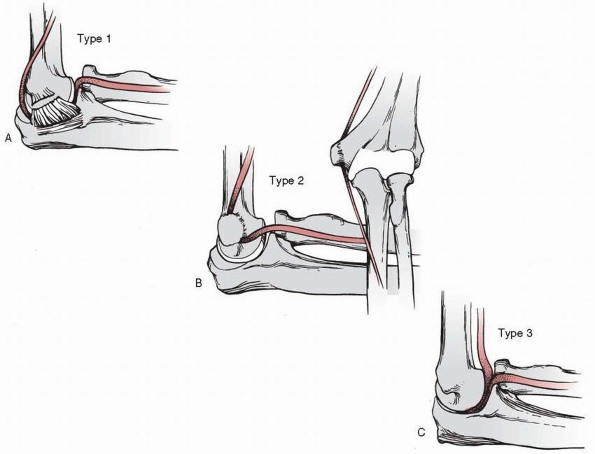

![]() |

FIGURE 16-16 Median nerve entrapment. A. Type 1. Entrapment within the elbow joint with the median nerve coursing posterior to the distal humerus. B. Type 2. Entrapment of the nerve between the fracture surfaces of the medial epicondyle and the medial condyle. C.

Type 3. Simple kinking of the nerve into the anterior portion of the elbow joint. (Redrawn from Hallett J. Entrapment of the median nerve after dislocation of the elbow. J Bone Joint Surg Br 1981;63: 408-412, with permission.) |

avulsion of the medial epicondyle or has a rupture of the medial

muscles at their origin and the ulnar collateral ligaments (see Fig. 16-16A).

This allows the median nerve, with or without the brachial artery, to

displace posteriorly. The nerve is especially prone to being entrapped

between the trochlea and the olecranon during the process of reduction

if the lateral displacement of the proximal radius and ulna is not

corrected before reduction. Hallett45

demonstrated in cadavers that pronation of the forearm while the elbow

is hyperextended forces the median nerve posteriorly during the process

of reduction making it vulnerable to entrapment. This type of

entrapment also has been reported by other authors.8,11,16,36,42,84,107,110,132